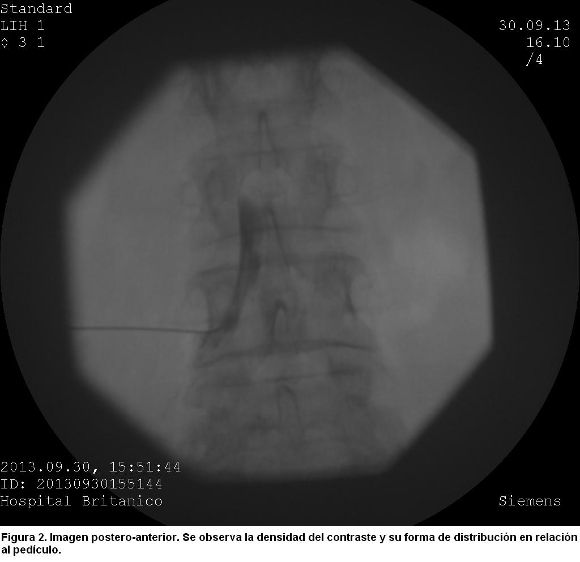

En el enfoque postero-anterior se observó una imagen densa y homogénea, que no dibujaba los márgenes inferior y medial del pedículo de L4 como ocurre cuando la inyección es periradicular (figura 2).